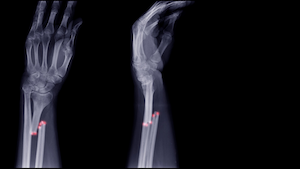

Your hands and your wrists are complex assemblages. They are comprised of:

- The “distal” ends of your two forearm bones, the radius and ulna, which extend between your elbows and wrists;

- Twenty-seven other bones in the wrist, hands, and fingers; and

- A complex network of muscle, nerves, and other tissue.

Since your hands and wrist are so complex, injuries to a single site often can have further-reaching consequences.

Hand and wrist injuries can take many different forms. Some of the most serious hand and wrist injuries caused by car crashes and slip-and-fall accidents include:

- Fractures: A fractured bone is a broken bone. Most fractures are caused by sudden falls, sports injuries, and motor vehicle collisions. Any bone in the upper arm, hand, or wrist could break in an accident, but some people are more vulnerable to certain types of injuries. Studies indicate that drivers in motor vehicle accidents, for instance, are more likely to injure their forearms than passengers.